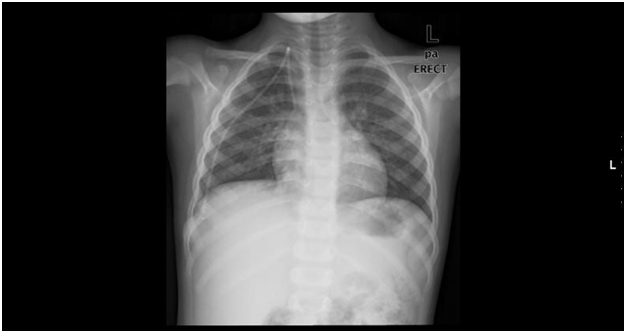

Five year old boy, a known case of acute lymphoblastic leukemia (T cell ALL) has started to receive chemotherapy using a Port-A-Cath which was inserted surgically (BARDPORT®, 10.8mm diameter, USA) (Figure 1). A chest radiograph has documented the normal position of the Catheter postoperatively (Figure 2). The patient received regular courses of chemotherapy following catheter insertion with no encountered problems.

Figure 2 Shows a normal position of the Port-A-Cath in the superior vena cava.

Nine months later and during routine follow-up, the patient presented with a history of trauma to the chest at the site of the Port-A-Cath which was found non-functioning and a chest radiograph showed that the catheter had been disconnected from the injection port and migrated into the heart (Figure 3). The patient was asymptomatic, admitted to the hospital and was kept under close monitoring. Disconnection of the catheter was suggested, so surgical intervention was performed and the injection port was removed successfully but due to difficult access it was recommended to remove the catheter by percutaneous retrieval technique after discussion with interventional cardiologist.

Figure 3 Shows the whole length of Port-A-Cath disconnected from its septum & migrated into the heart making a large curve in the right ventricle.